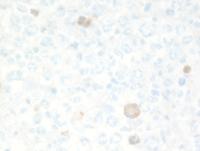

Immunostains in GZL

Immunostains show that the large cells are uniformly positive for CD20, and Oct-2. Additional B-cell markers including CD79a, Pax5 (not shown) were also positive indicative of a well preserved B-cell program. The backgound is rich in CD3+ T-cells. There was also weak CD5 expression in the large cells (not shown). Rare large cells express weak CD30 but there is strong uniform CD15 with weak variable Mum1 (usually strong in pure cHL).

Notably, most of the lymphoma cells are moderately positive for PD-L1.